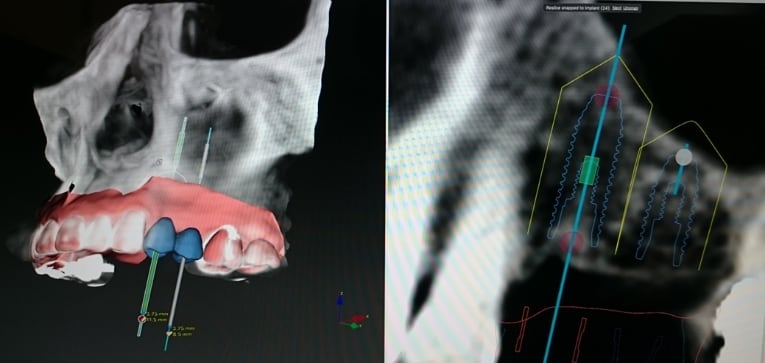

DTXによるシミュレーション

最終的な歯の形態をどのようにするかを決定し、これをスキャンしてCTデータと重ね合わせ、プランニングソフト(DTX)上で視覚化します。

DTXから適切なインプラント埋入位置をプランニングし、実際の手術で使用する「サージカルテンプレート」が完成します。このサージカルテンプレートを使用することで、シミュレーションで決定した位置に正確にインプラントを埋入することができます。